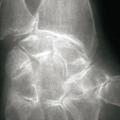

La forme pseudorhumatoïde est rare (5 %), simulant une polyarthrite rhumatoïde. L’arthrite chronique à PPC se présente comme une oligo- ou une polyarthrite, avec parfois des signes systémiques d’inflammation (élévation de la vitesse de sédimentation et de la protéine C-réactive [CRP]). La superposition d’accès aigus microcristallins est évocatrice de ce diagnostic. Il s’agit d’un diagnostic différentiel de polyarthrite rhumatoïde du sujet âgé ou de pseudopolyarthrite rhizomélique. Le diagnostic repose sur la mise en évidence des cristaux de PPC, même si les radiographies standard sont évocatrices. L’atteinte radiographique associe des calcifications des cartilages articulaires (fig. 7) et des fibrocartilages (fig. 8, 9, 10 et 11) [à rechercher systématiquement sur les radiographies de poignets, genoux et symphyse pubienne]. La mise en évidence d’une chondrocalcinose sur des radiographies standard renforce le diagnostic de rhumatisme à PPC mais l’absence de dépôts calciques ne l’élimine pas (la sensibilité de la radiographie standard étant imparfaite). L’échographie peut mettre en évidence des dépôts de PPC, qui apparaissent comme une fine bande hyperéchogène au sein des cartilages hyalins et comme des points scintillants dans les fibrocartilages ou dans la membrane synoviale. La sensibilité de l’échographie est bien supérieure à celle de la radiographie standard. Le scanner peut également mettre en évidence des dépôts calciques évocateurs, notamment au niveau du rachis ou du bassin qui sont plus difficilement explorés par les radiographies et l’échographie.